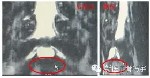

本病例为作者博士课题所进行的研究,使用磁共振脊髓成像术(MRM)能够根据观察到硬膜囊内脑脊液充盈改变,直接判断硬膜囊所受压迫及程度。硬膜囊受到压力时,其所含脑脊液受阻减少或消失,这种解剖学特点就决定了其是一个天然的压力感受器。

治疗前MRM椎管三维重建图像,显示腰椎管狭窄患者由于椎管狭窄硬膜囊中断。

脊柱定点旋转复位法治疗后,MRM椎管三维重建图像显示脑脊液通过狭窄阶段使硬膜囊末端明确延长,受压硬膜囊较治疗前明显充盈,由此推测脊柱定点旋转复位法可以使硬膜囊所受压力减小,从而解除或缓解椎管狭窄症状。